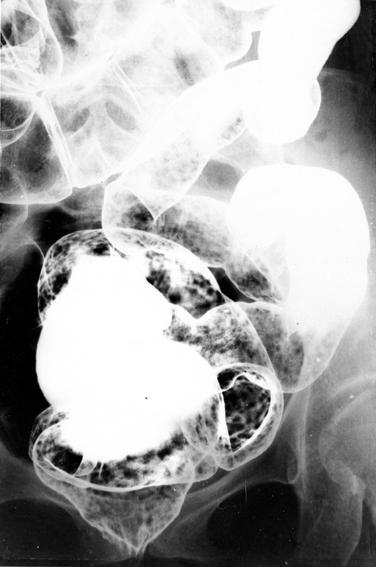

미만성 양성 림프여포 증생증

미만성 림프여포 증생증(case-2)

종양양 병변/양성 림프여포성 용종증

대장/2구역 이상의 대장에 걸치는 것

X-P

1~9